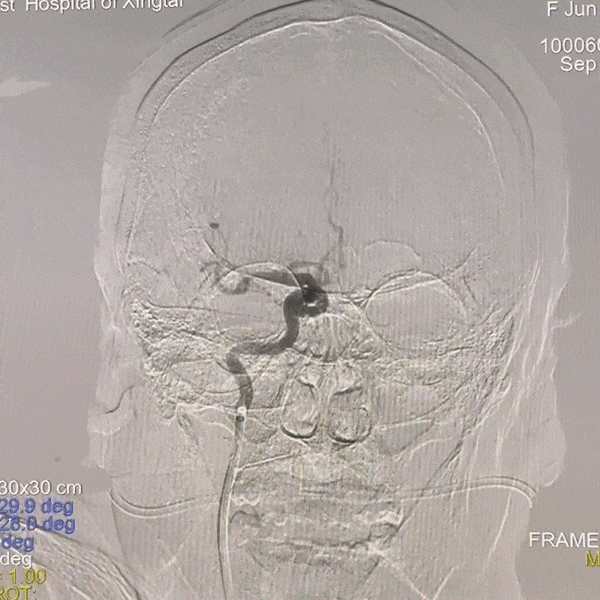

手术过程

通路建立:经桡造影显示Ⅲ型弓,病变为右侧颈内动脉C4段动脉瘤,患者桡动脉纤细不适合经桡治疗,故选择经股动脉应用赛诺神畅APEX TRA GC™5F-130 SIM2导引导管超选右颈,同轴长鞘建立通路。

动脉长鞘怎么置入一技之“长”丨经桡及经股困难入路应用赛诺神畅APEX TRA GC™导引导管建立通路病例合集_https://www.jmylbn.com_新闻资讯_第20张

Ⅲ型弓

动脉长鞘怎么置入一技之“长”丨经桡及经股困难入路应用赛诺神畅APEX TRA GC™导引导管建立通路病例合集_https://www.jmylbn.com_新闻资讯_第21张

SIM2导管成袢

动脉长鞘怎么置入一技之“长”丨经桡及经股困难入路应用赛诺神畅APEX TRA GC™导引导管建立通路病例合集_https://www.jmylbn.com_新闻资讯_第22张

超选入无名动脉

跟进长鞘至右侧颈内动脉。

动脉长鞘怎么置入一技之“长”丨经桡及经股困难入路应用赛诺神畅APEX TRA GC™导引导管建立通路病例合集_https://www.jmylbn.com_新闻资讯_第23张

栓塞动脉瘤;致密栓塞AN后复查造影。

动脉长鞘怎么置入一技之“长”丨经桡及经股困难入路应用赛诺神畅APEX TRA GC™导引导管建立通路病例合集_https://www.jmylbn.com_新闻资讯_第24张

动脉长鞘怎么置入一技之“长”丨经桡及经股困难入路应用赛诺神畅APEX TRA GC™导引导管建立通路病例合集_https://www.jmylbn.com_新闻资讯_第25张